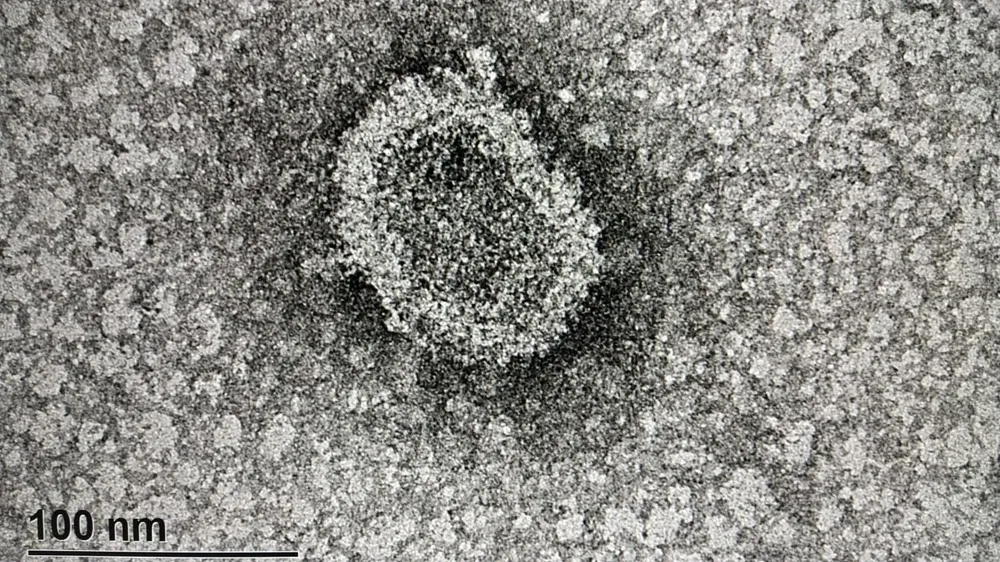

Quienes tienen dos dosis de la vacuna de Sinovac (Coronavac) y recibieron un refuerzo anticovid con Pfizer tienen 20 veces más de anticuerpos contra el virus, según un estudio uruguayo presentado este viernes por el Instituto Pasteur y la Universidad de la República (Udelar). Se trata de un aumento “muy importante de anticuerpos”, expresó Sergio Bianchi, investigador del Instituto Pasteur.

Previo a la vacunación, las 53 personas de un subgrupo –en total son 200 personas–, no tenían anticuerpos, declaraban no haber tenido covid-19 y era “esperable”, según añadió Bianchi. En resumen, si se compara la segunda extracción con la cuarta, la cantidad de anticuerpos aumentó 20 veces. “Nos parece un aumento significativo”, enfatizó.

Una de las muestras fue previo al inicio de la vacunación; otra a los 18 días promedio de recibida la segunda dosis (Pfizer y Coronavac); la tercera a aproximadamente a 80 días luego de la segunda dosis; y la última a quienes recibieron tercera dosis de Pfizer, que tengan dos iniciales de Coronavac, con 18 días en promedio, posterior.

Desde principios de marzo de 2021 se realiza en el Instituto Pasteur de Montevideo un proyecto de investigación para estudiar la evolución de los niveles de anticuerpos específicos anticovid en el personal del instituto. Esta propuesta fue aprobada por el Comité de Ética y más de 200 integrantes aceptaron participar voluntariamente.